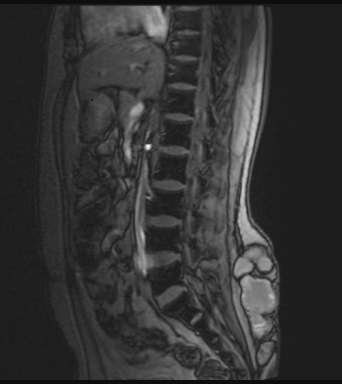

A 26-year-old otherwise healthy man, originally from Ethiopia and having recently immigrated from Kenya to Canada, presented with increasing pain, swelling, and discharge from a chronic wound to his lower back. The symptoms had persisted for years following childhood trauma from falling into a well. No formal wound care was sought at the time, and he experienced chronic discomfort and intermittent drainage. He had no other significant past medical history and was not immuno-compromised. He underwent multiple debridement and antibiotic courses in Kenya without resolution. Nine months after arriving in Canada, he presented to an emergency department for worsening symptoms. Three months prior to his emergency visit, he was evaluated by his family physician, and underwent MRI imaging, which revealed a multiloculated subcutaneous collection without bony involvement measuring 11.6cm x 11.8cm x 3.7 cm (Fig 1A). He received clarithromycin for a presumed chronic hematoma or seroma. However, symptoms persisted, prompting his presentation to acute care.

Imaging: MRI and CT of the lesion revealed a multiloculated subcutaneous collection without bony involvement.